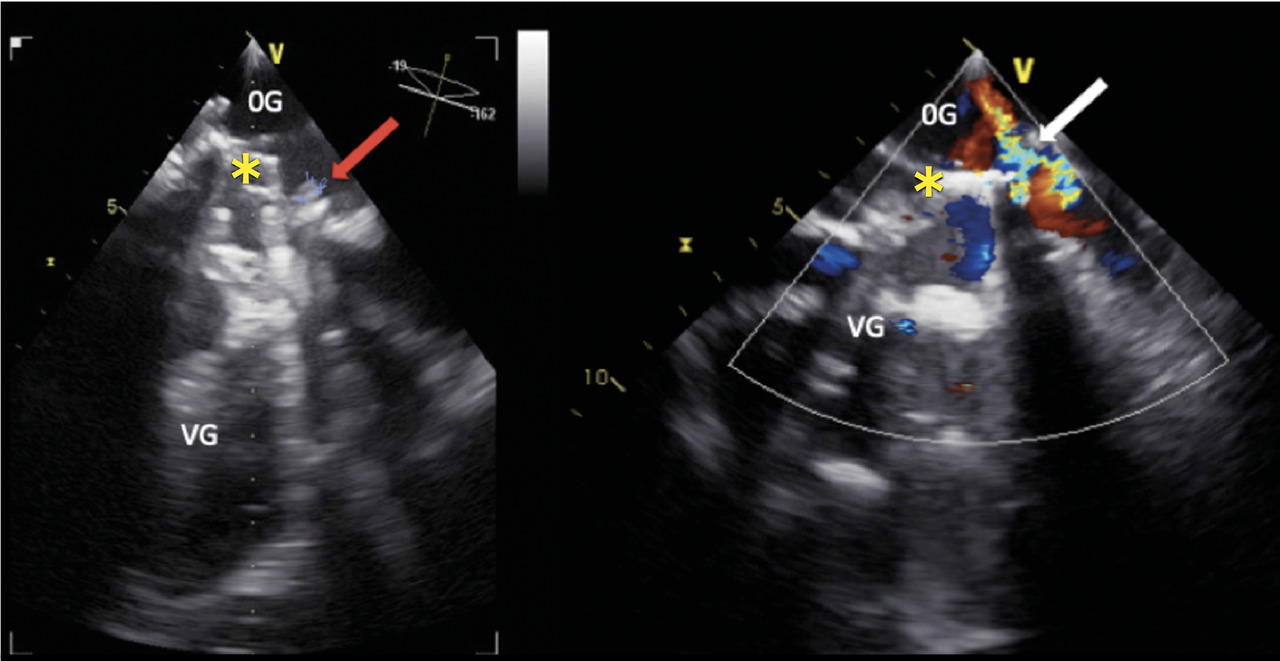

Cette femme de 67 ans avait une asthénie et par intermittence des urines sombres. Une insuffisance mitrale rhumatismale avait été traitée 22 ans auparavant par remplacement valvulaire chirurgical. Le bilan biologique révélait une anémie (7,6 g/dL) normochrome normocytaire régénérative (taux de réticulocytes à 278 000/mm3), un taux de lacticodéshydrogénase à 2 688 UI/L, un taux d’haptoglobine inférieur au seuil de détection et un taux normal de bilirubine totale. Le frottis sanguin (fig. 1 ) notait de très nombreux schizocytes (plus de 500/1 000). L’échocardiographie transœsophagienne (ETO)montrait la présence d’une végétation et une fuite prothétique (fig. 2 ). Il s’agissait d’une endocardite infectieuse à Pseudomonas aeruginosa compliquée d’une désinsertion de valve prothétique.